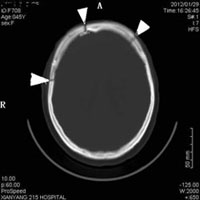

据悉,患者,女性,以“头痛、双眼失明1月”为主诉入院。查体:左侧视乳头轻度原发性萎缩,右侧视乳头水肿。增强头颅MRI示左侧鞍上及鞍旁见一大小约4cm×4cm×3cm的巨大脑膜瘤。肿瘤与左侧颈内动脉、大脑中动脉、大脑前动脉、左侧丘脑及下丘脑、左侧视神经及视交叉、左侧中脑大脑脚等重要结构关系密切。如此巨大的肿瘤以及特殊的位置,决定了手术的极高难度。术中损伤上述任一结构,都将产生灾难性的后果。术前经神经外科全体医务人员讨论,结合特殊病情,决定采用新式的双额翼点联合开颅前床突脑膜瘤切除术,该联合入路的优势是能分别从纵裂入路和侧裂入路暴露肿瘤。准备完善后,由我院神经外科二病区主任左毅博士主刀、副主任医师王国伟、主治医师陈尚军协助,术中经历了大出血肺水肿等多道难关,最终在手术显微镜下为患者进行肿瘤切除术。通过精细操作,顺利将肿瘤切除。

前床突脑膜瘤位于颅底的中央区域,位置特殊,与周围许多重要结构关系密切,手术难度很大。在没有手术显微镜的经典神经外科时代,前床突脑膜瘤的全切率低、死亡率高、并发症多。据介绍,利用手术显微镜的立体放大、同轴照明及良好景深,彻底改变了以往的手术方式,使前床突脑膜瘤的手术效果有了极大的提高。但术者必须具备足够的显微解剖知识及娴熟的显微外科操作技术。